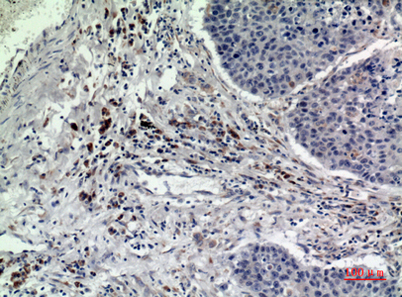

| Dilutions: | Western Blot: 1/500 - 1/2000. IHC-p: 1/100-1/300. ELISA: 1/20000. Not yet tested in other applications. |